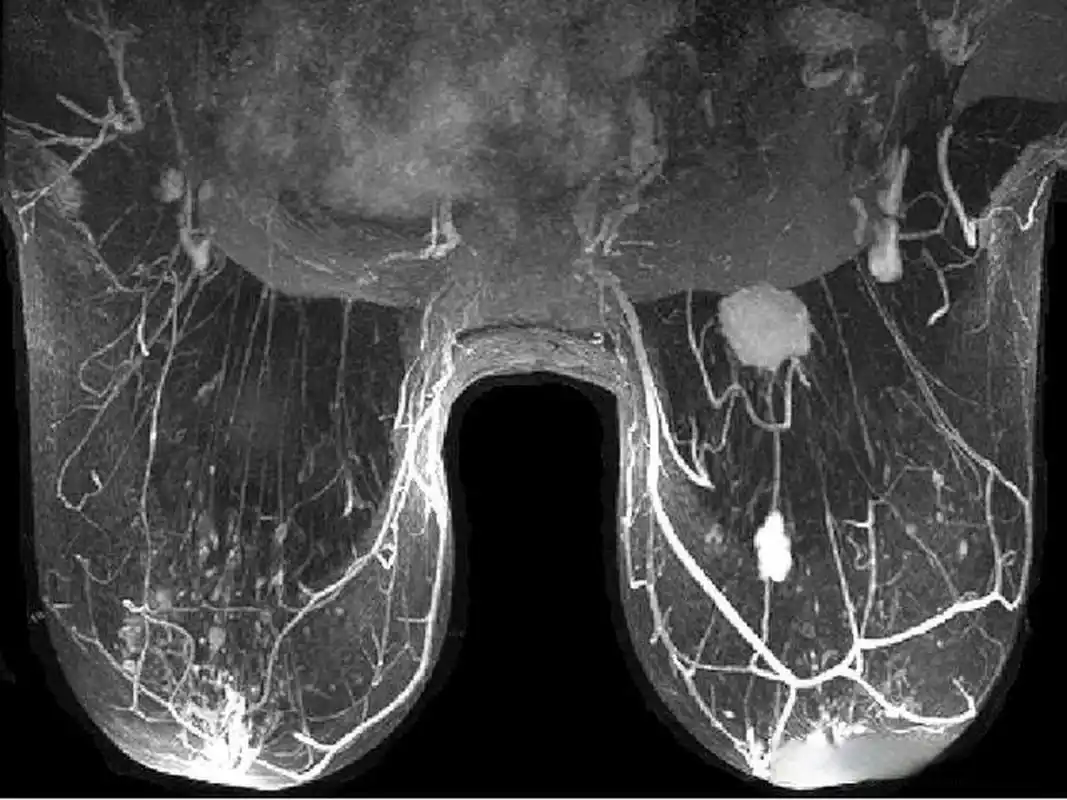

乳腺磁共振检查技术

扫盲乳腺mri怎么扫描

乳腺常见病变的mri表现

乳腺病变磁共振基本征象分析与诊断进展

磁共振乳腺影像报告和数据系统